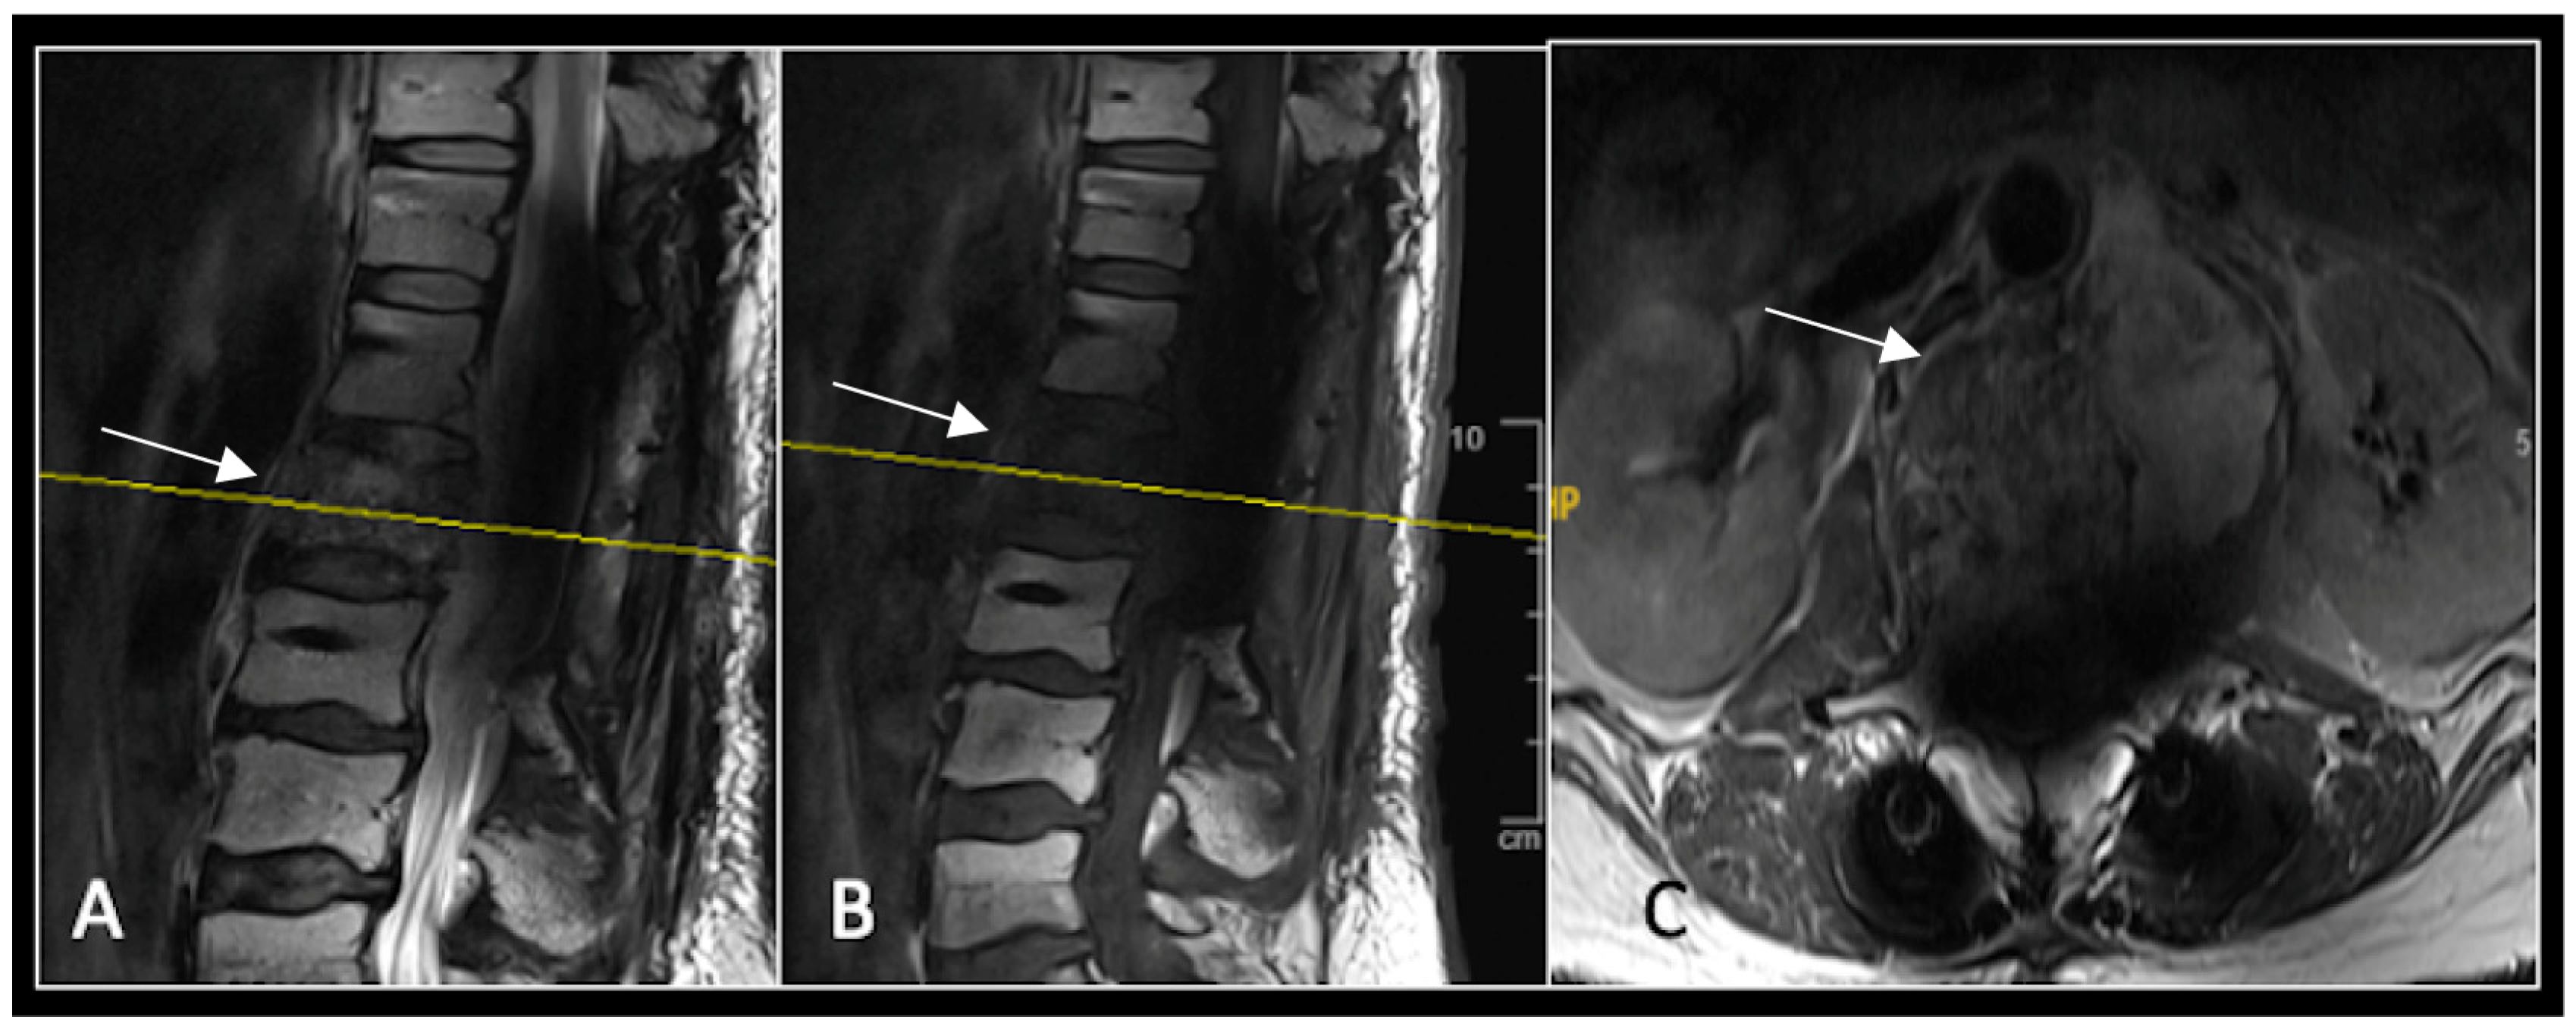

This 56-year-old lady was diagnosed with a biopsy-confirmed L2 chordoma (Figure 11). She underwent posterior decompressive separation surgery and instrumental stabilisation T12-L4 using carbon-based implants (Figure 12). Surveillance imaging at 6 months and 12 months post-separation did not show any progression of residual tumour disease (Figure 13 and Figure 14).

Figure 11.

RI demonstrating a lobulated destructive lesion (arrow) with significant epidural extension and compression at L2. The yellow line on the sagittal images denotes the level of the axial image. (A) T2W sagittal; (B) T1W sagittal; (C) T2W axial.